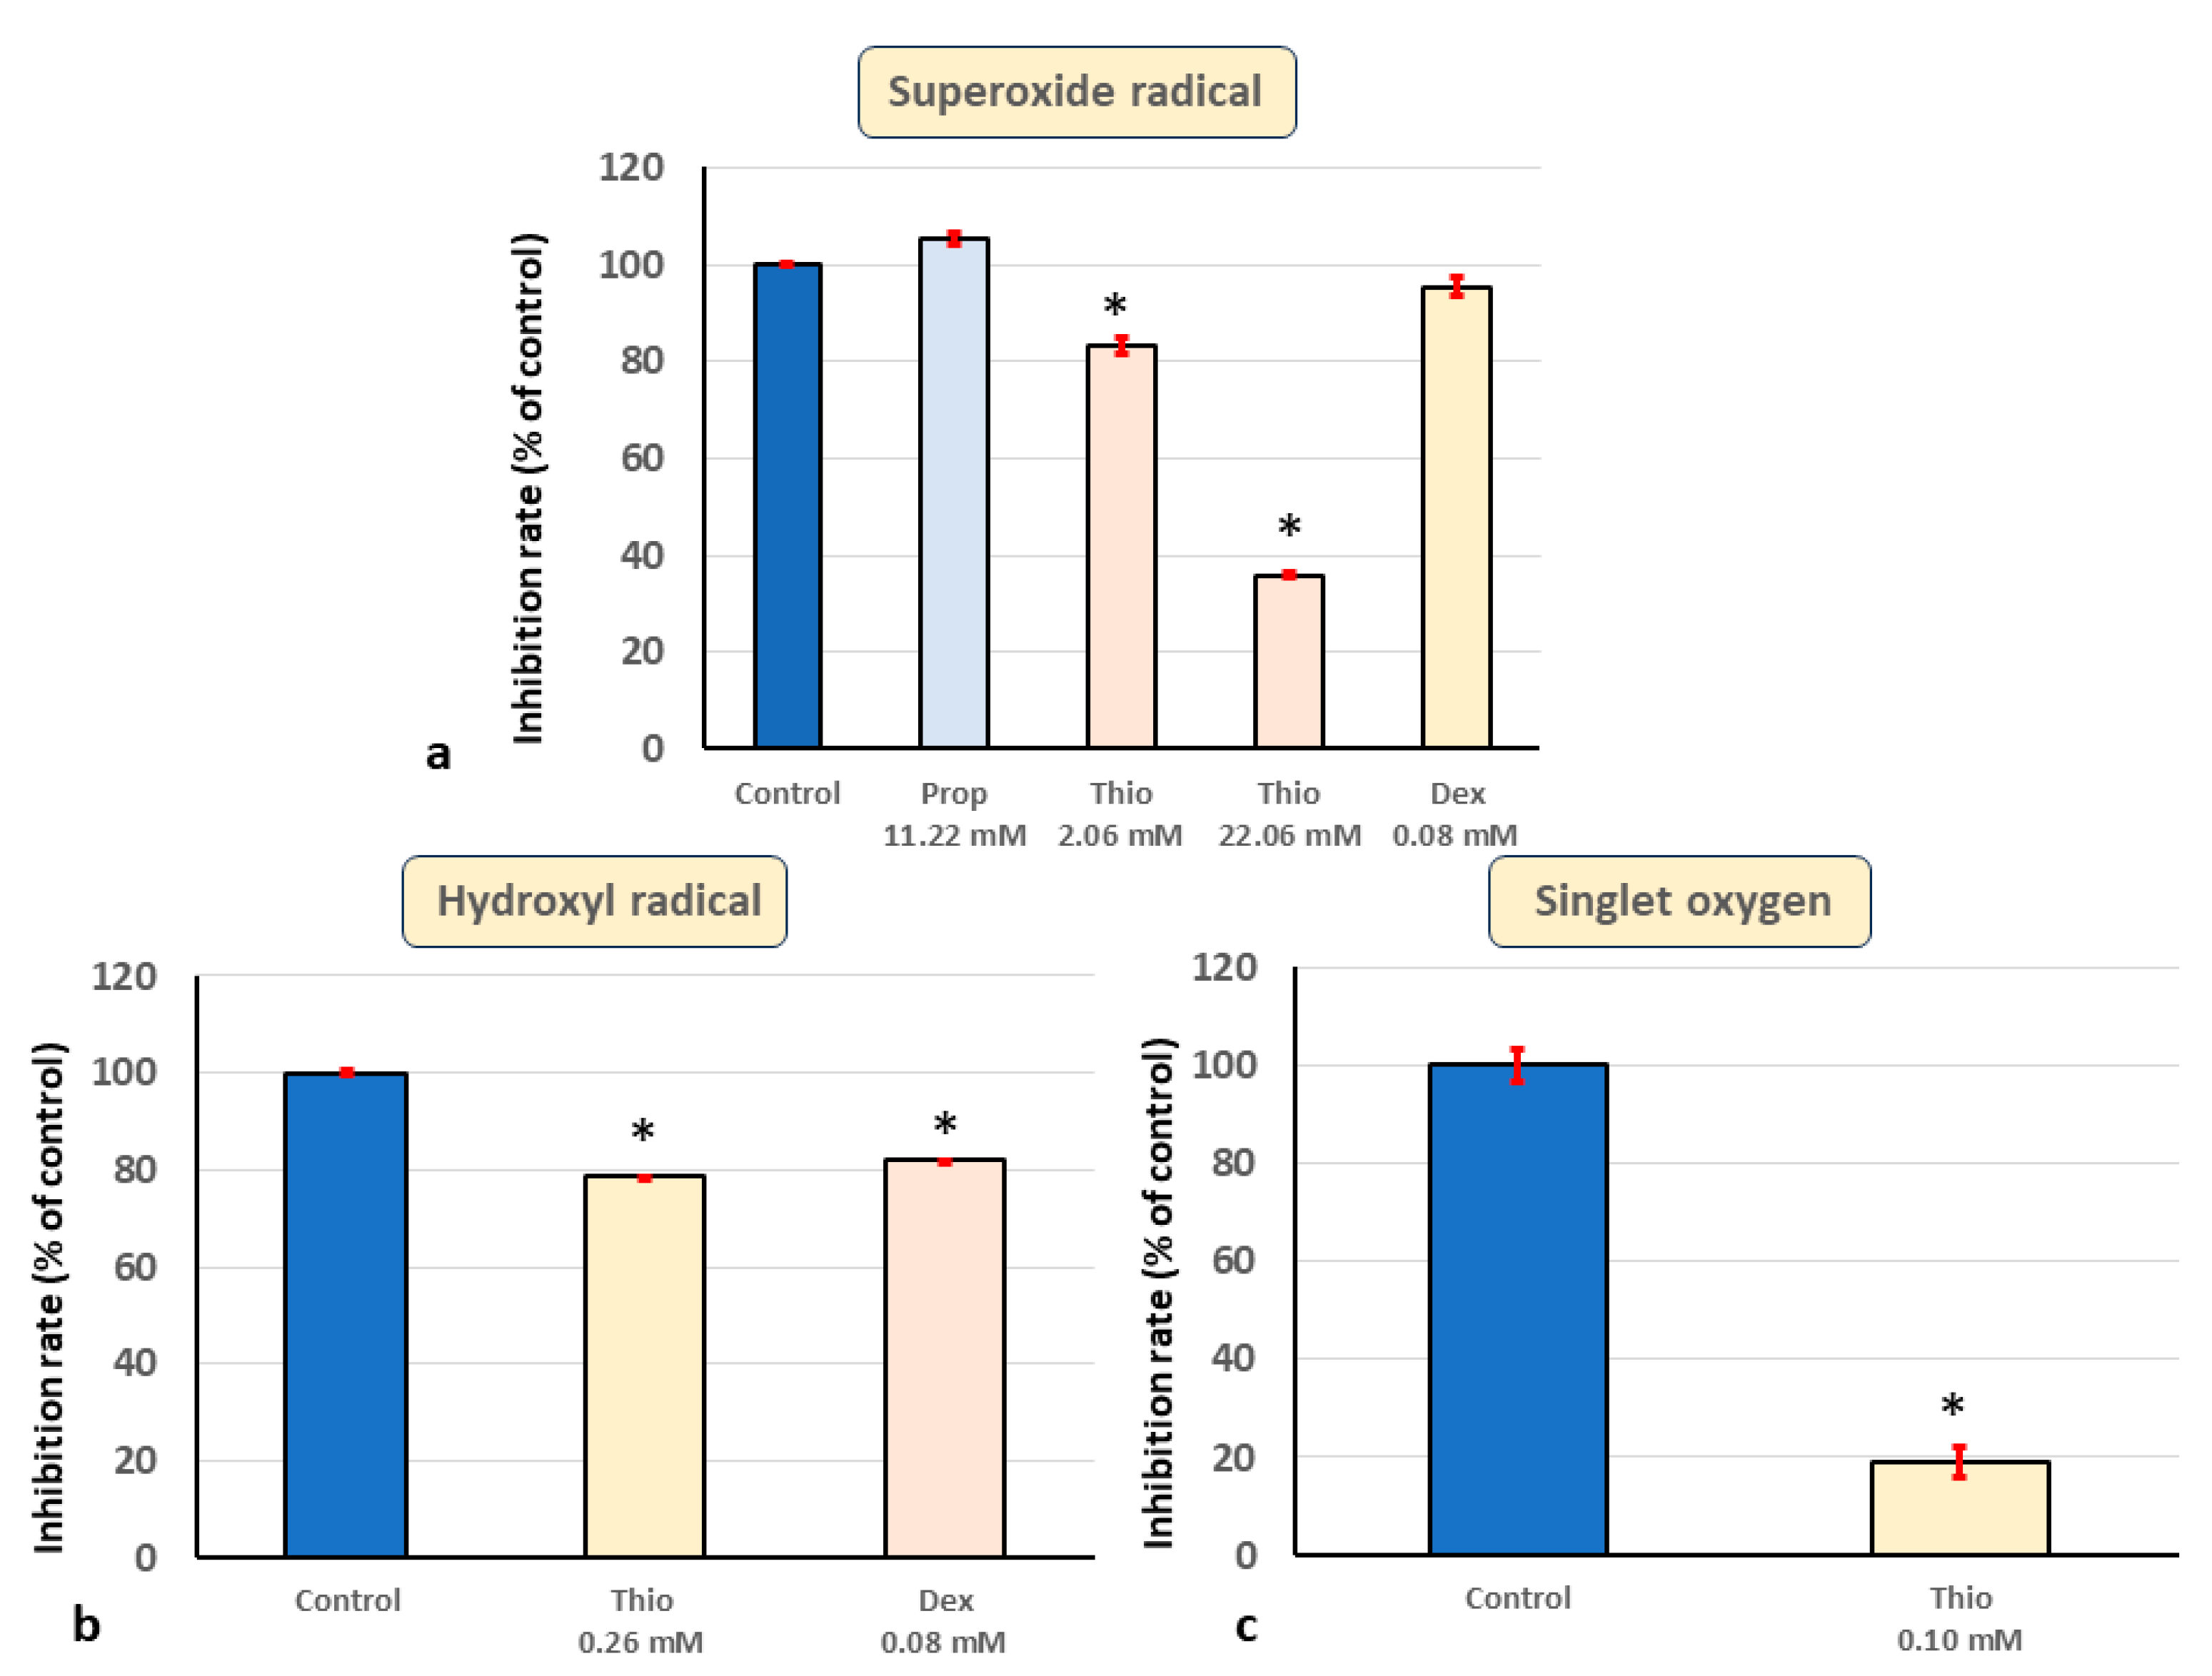

2.2. In Vitro ESR Method

3. Results